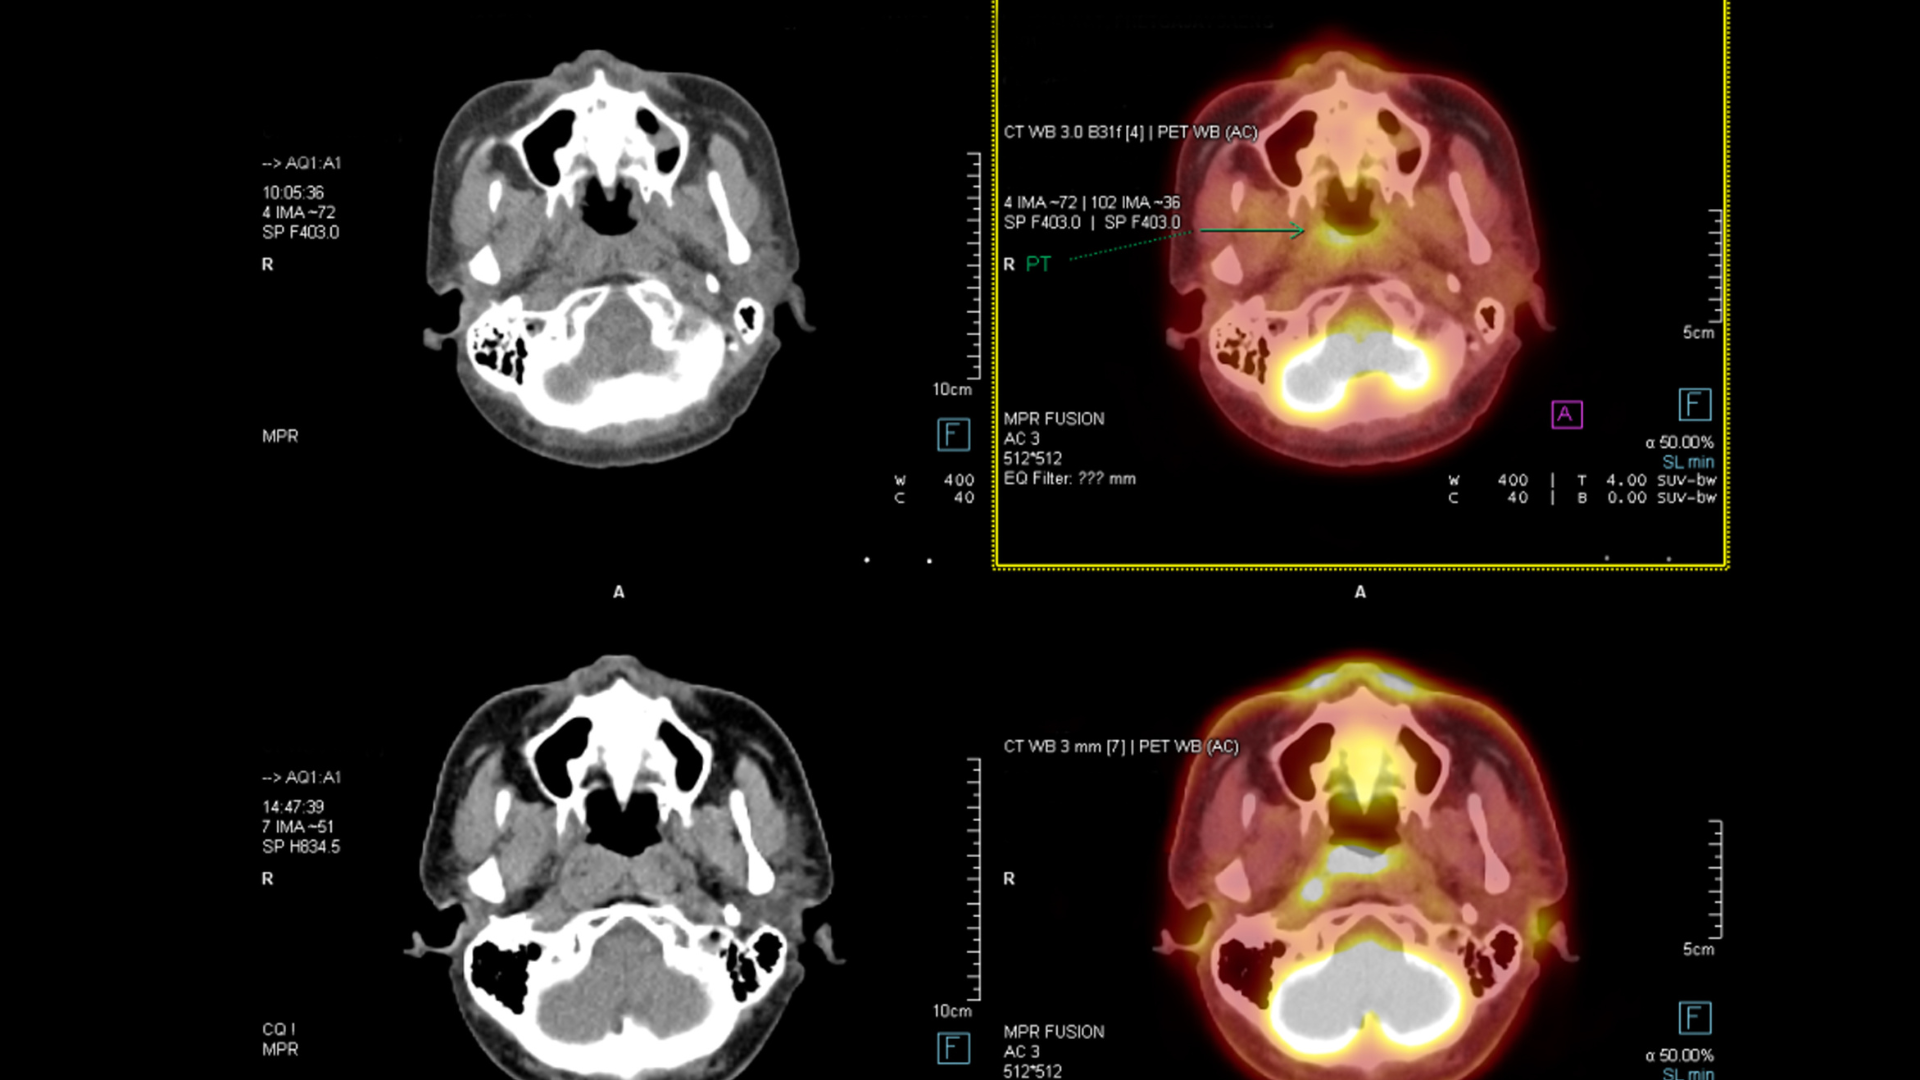

- Nghi ngờ xuất huyết não, u não hoặc tổn thương cấu trúc nội sọ.

Lợi ích của chụp CT đầu

Chụp CT giúp bác sĩ quan sát rõ xương sọ, não và các bất thường bên trong. Từ đó, hướng điều trị được xây dựng chính xác và kịp thời, hạn chế biến chứng nguy hiểm.